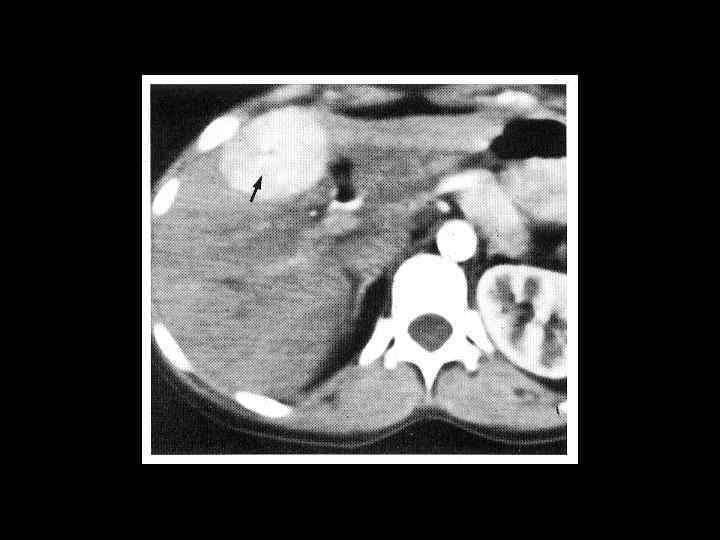

Клиническое наблюдение. Пациентка К, 1966 г. р.

Та же пациентка